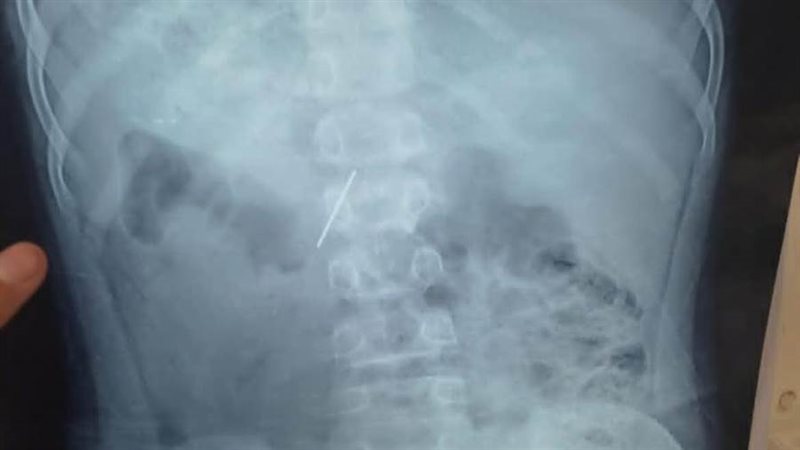

الأطفال التخصصي ينجح في استخراج "مسمار دباسة" اخترق جدار بطن طفل بالقليوبية

نجح قسم جراحة الأطفال بمستشفى الأطفال التخصصي ببنها، في استخراج مسمار دباسة كراسة اخترق جدار بطن طفل واستقر داخل التجويف البطني، بعد تدخّل جراحي متقدّم جمع بين المنظار الجراحي وجهاز السي أرم لتحديد الموقع بدقة متناهية.

وصل الطفل إلى المستشفى وهو يعاني ألمًا شديدًا وقلقًا أسرته، وكشفت الفحوصات الأولية وجود جسم غريب حاد داخل البطن. قرار الفريق كان حاسمًا، استئصال المسمار بأسرع وآمن طريقة ممكنة لتفادي أي مضاعفات قد تهدد حياة المريض.